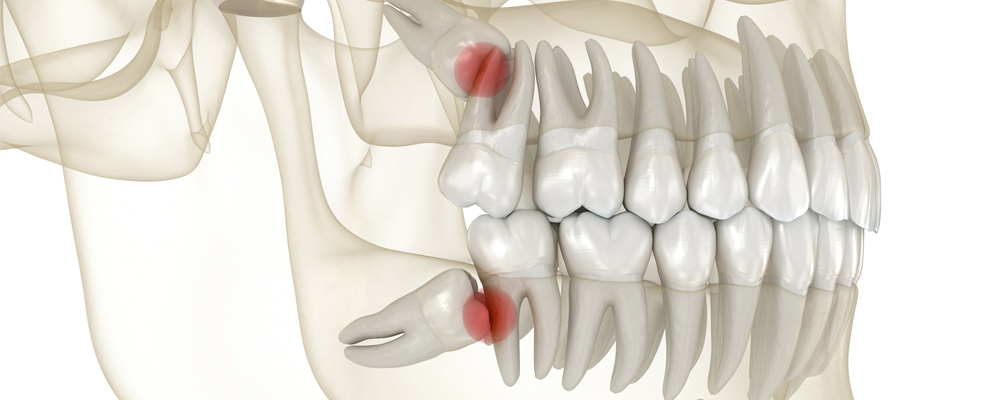

親知らずは真っ直ぐに生えてこないことが多い

昔は親知らずが正しく生えてくる人が過半数を占めていましたが、最近は食生活の変化などの影響により顎が小さく、親知らずが正常(まっすぐ)に生える割合は全体の約10〜30%程度で、残りの約70〜90%は斜め・真横に生えるなど、何らかのトラブルを抱えるケースが多いです。

- 斜めに生える

- 横向きに埋まっている

- 一部だけ歯ぐきから出ている

- 完全に骨の中に埋まっている

③ 噛み合わせや歯並びに影響する場合

親知らずが横向きになっている場合、手前の歯に後ろから押すような力がかかります。親知らずが手前の歯を強く押くことによって、歯並びが悪くなってしまうことがあります。また強い圧力がかかることで、前歯の歯並びに影響を与える可能性もあります。矯正治療後の後戻りを防ぐ観点からも、必要に応じて抜歯をすすめることがあります。